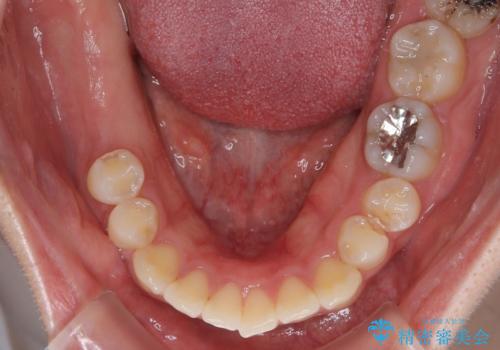

「1年前に抜歯した右下の奥歯にインプラントを入れたい」とのことで来院されました。

インプラント希望部位は右下第一大臼歯と第二大臼歯です。

しかし、噛み合わせの相手である右上の第二大臼歯が、長期間噛み合う歯がなかった影響で**挺出(歯が下に伸びてくる状態)してしまっており、このままではインプラントを埋入して被せもの(上部構造)を入れるためのスペースが不足している状態でした。